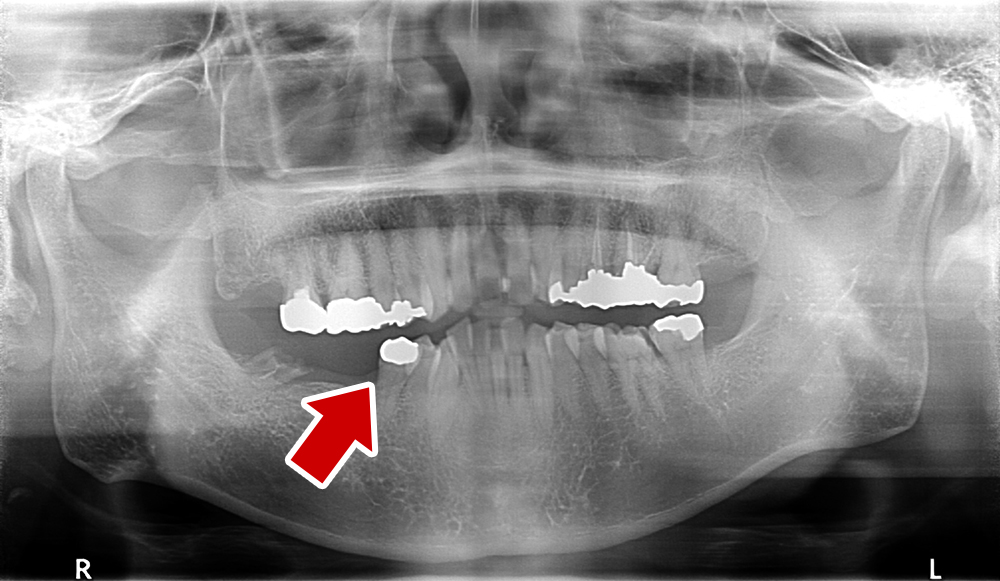

60歳 男性 歯科大学病院 教授からの紹介。ご本人は産婦人科医

- 主訴

- 左下に歯が無くて食事がしずらい

- 処置内容

- 2本インプラント埋入+再生処置。

- 治療費用

- 下顎 約80万円(税込)

- 治療期間

- 下顎:6か月

- リスク

-

術後の腫れ、痛み(ピークは3日後、1週間で軽減)

上部構造物、仮歯の破折、人工歯根脱落リスクがあります

- その他

- 歯科大学病院 教授からの紹介。ご本人は産婦人科医